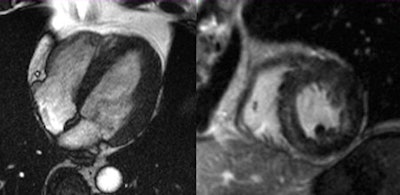

Acute myocardial infarction. General MRI features include regional wall motion abnormality, myocardial edema corresponding to regional wall motion abnormality, subendocardial to transmural late-enhancement (depending on infarct severity), and embolic infarction in side wall of left ventricle. All images courtesy of Dr. Tilman Emrich."Our study demonstrated that, even if catheterization results are equivocal, many conditions of the heart muscle were prevalent in these patients," Emrich emphasized.